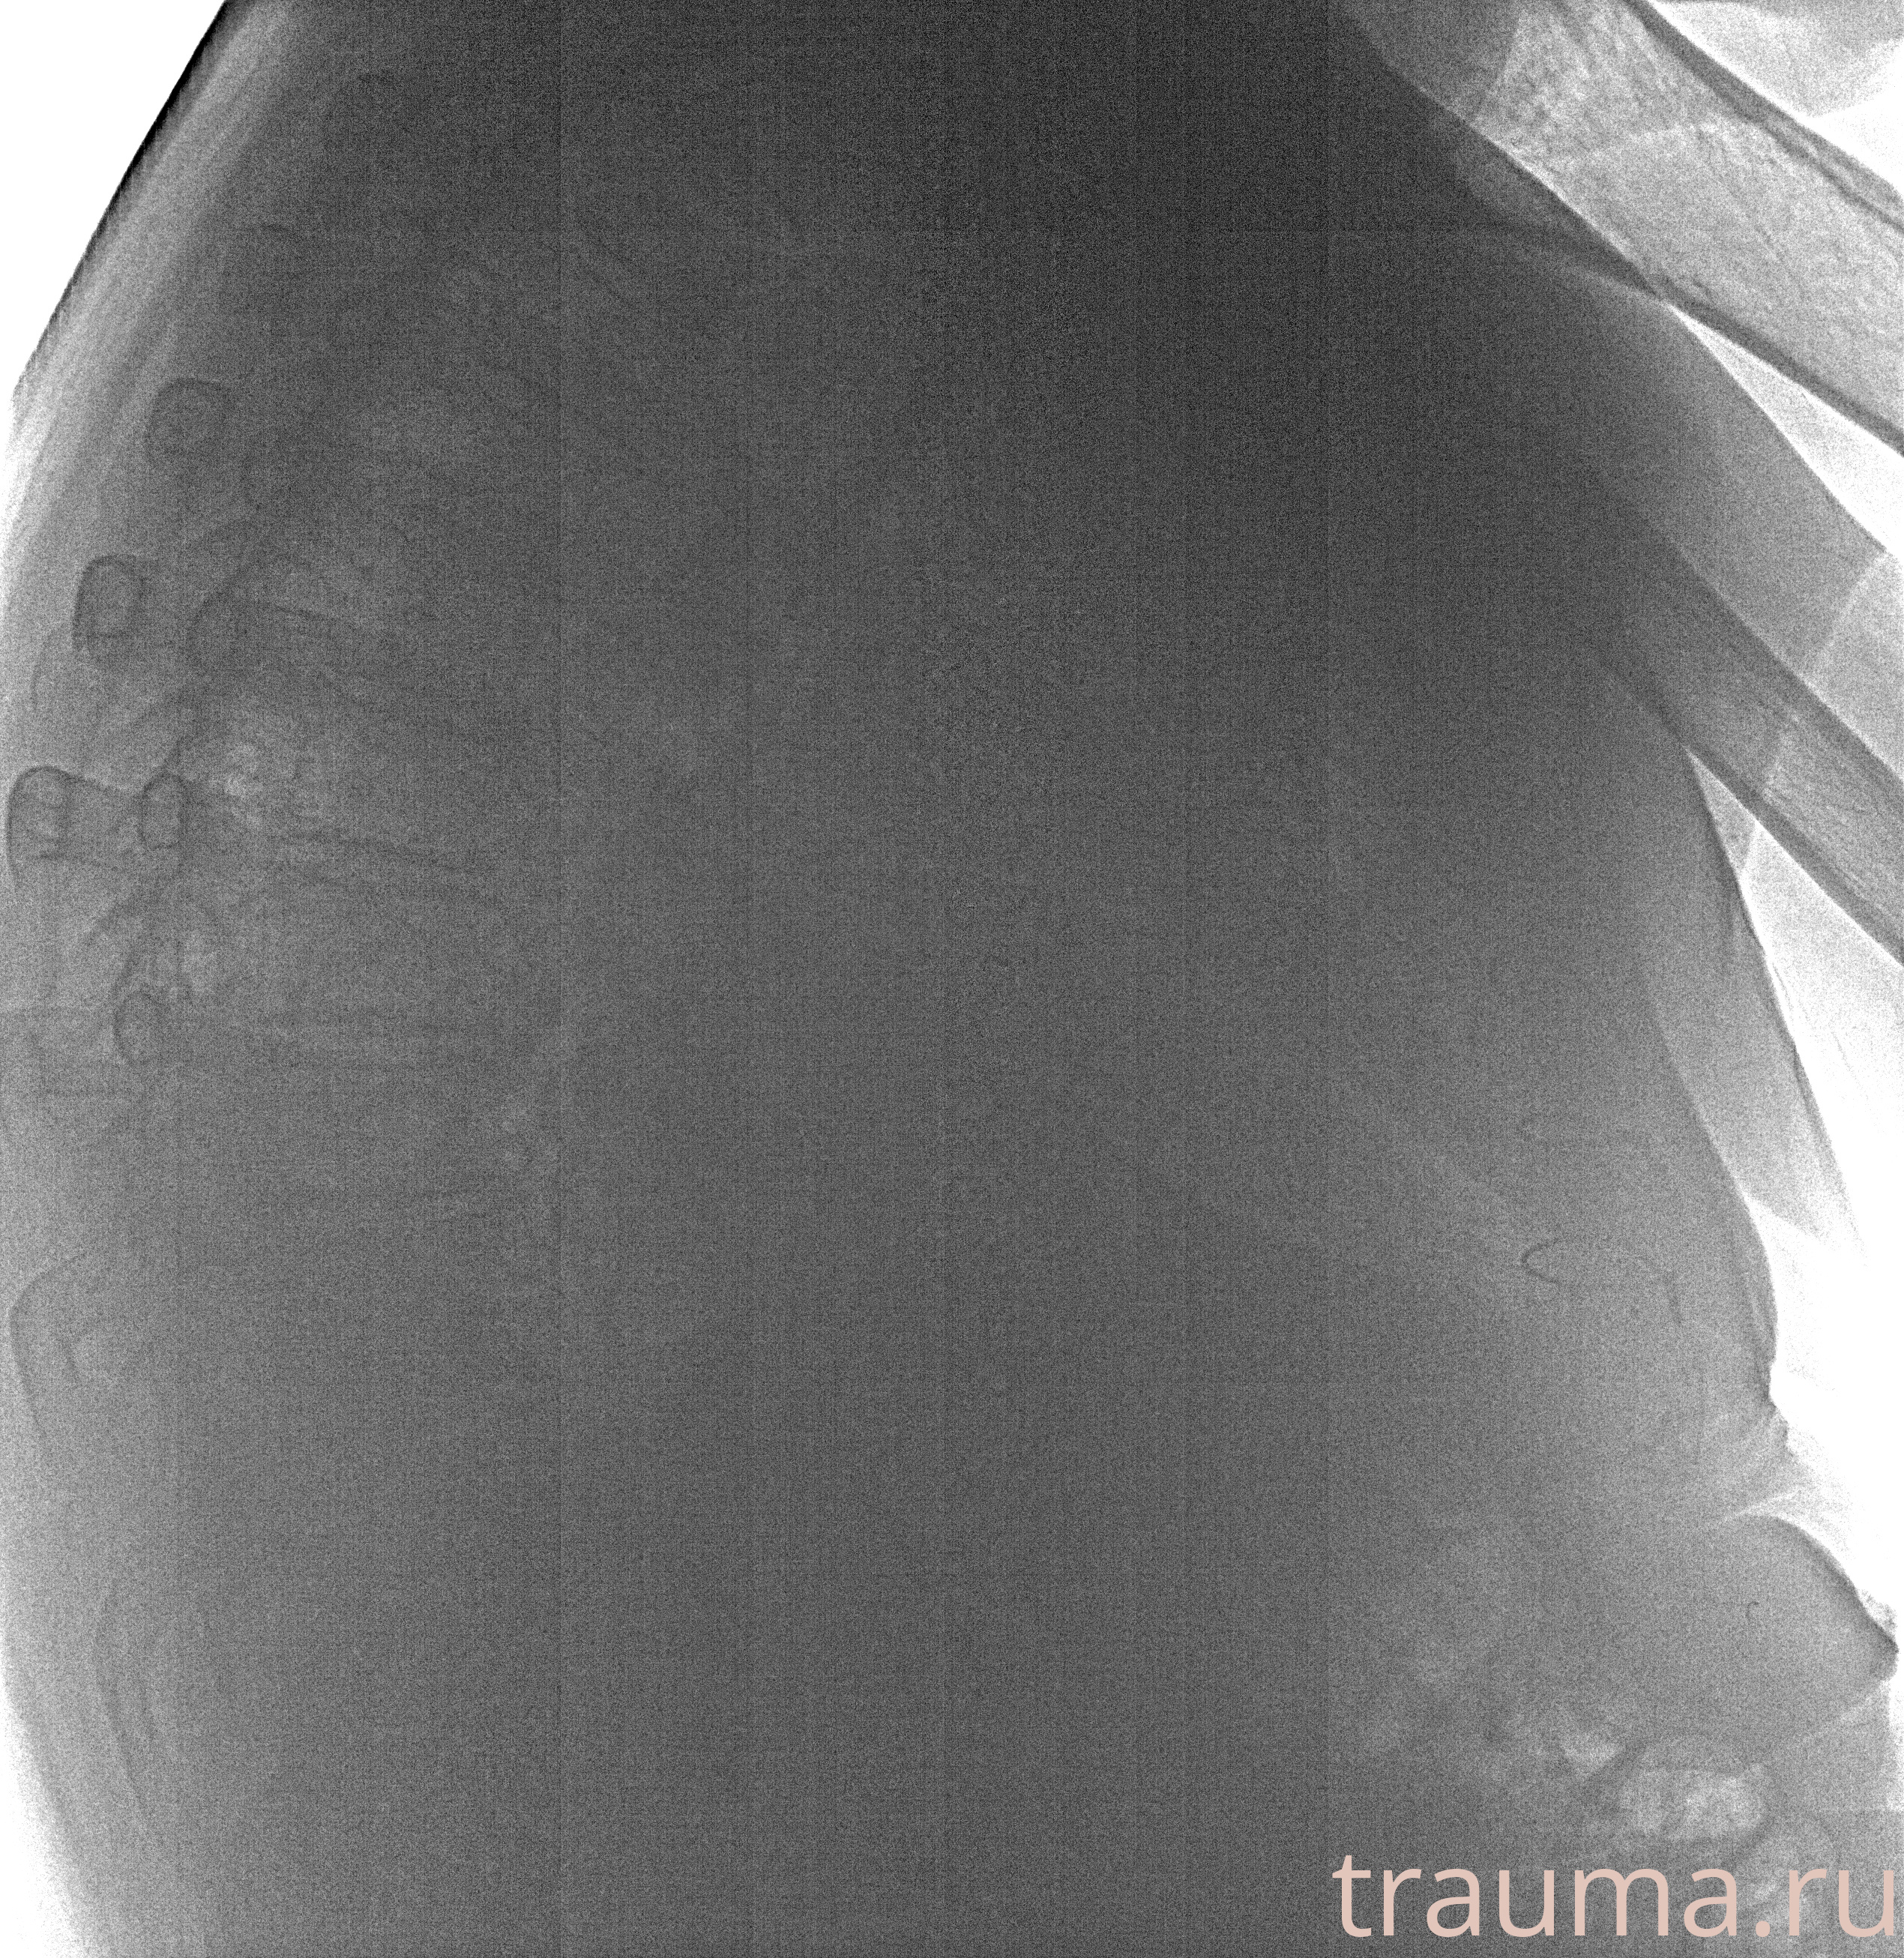

Рентген на дому: по вашему адресу приезжает врач-рентгенолог, травматолог-ортопед с мобильным рентгеновским аппаратом, проводит диагностику травмы или заболевания, делает необходимые рентгенограммы, дает рекомендации по дальнейшему лечению. Получить качественные снимки в домашних условиях возможно благодаря уникальной методике, разработанной МосРентген Центром для института  Склифосовского